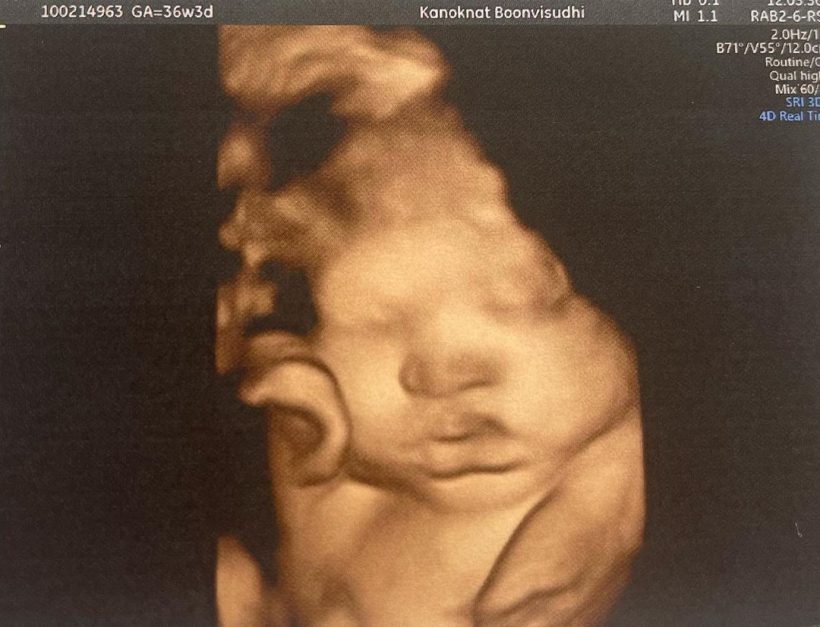

นับว่าเป็นครั้งแรกที่ “น้ำชา” เผยภาพอัลตร้าซาวด์ลูกชายครั้งแรก ผ่านอินสตราแกรม @namcha_tea พร้อมระบุข้อความว่า “หน้า @babynamtalay เหมือน คุณพ่อ หรือ คุณแม่ น้า?? ลูกกลับหัวแล้ววว อีกไม่เกิน 3 อาทิตย์เจอกันนะครับลูกมี้ เจ็บท้องหลอก เจ็บท้องจริง จะแยกออกมั้ยนี่ ไปรอแถว รพ. เลย อ่านคู่มือจบไปหลายเล่มจนไม่มีอะไรอ่านแล้ว…. ตื่นเต้นปนกลัวปนหลายอย่างมากค่ะ… ฮือๆๆ จะผ่านไปได้มั้ย… ต้องได้ๆ แม่ๆเป็นยังไงกันบ้างคะ?? ติดตามวันแรกของลูกพร้อมๆกันนะคะ ฝาก IG ลูกมี้ชา กับแด้ดวาว ด้วยนะคะ @babynamtalay”